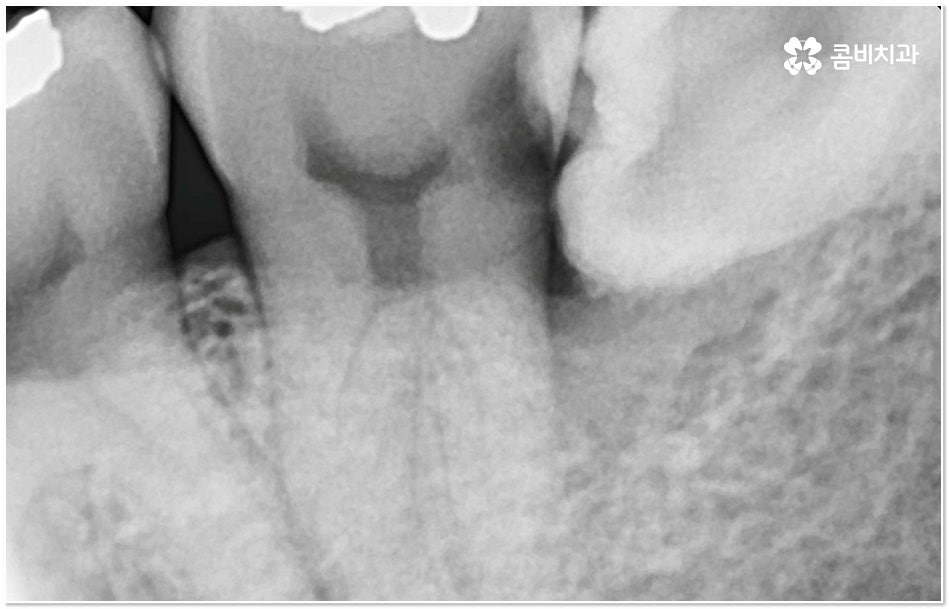

특히 그 중에서도 사랑니와 어금니 사이에 생긴 치아 사이 충치 는 구강 내 가장 안 쪽에 있기 때문에 제 때 발견하기도 어렵고 위치상 치료하기가 쉽지 않아서 병증의 진행 여부 및 상황에 따라 사랑니 뿐만 아니라 어금니까지 발치를 해야 하는 안타까운 상황에 이를 수도 있으니 그 전에 알맞은 대처를 해 주시는 것이 필요할 거예요.

충치는 입 안에 남아있는 음식물 찌꺼기 속 당분을 세균이 먹는 과정에서 배출되는 산으로 인해 치아가 부식되어 생기는 질환으로 보통 치아가 맞물리는 교합 부위인 치아의 윗면, 즉 저작면에만 충치가 생긴다고 생각하기 쉽지만 치아와 치아 사이에 생기게 되는 경우도 종종 있으며 특히 사랑니와 어금니 사이에 치아 사이 충치 가 생기면 말씀드린 것처럼 발견 및 치료가 굉장히 까다로워 질 수 있는데요.

사랑니와 어금니 인접면에 치아 사이 충치 가 발생할 경우 육안으로도 보기 힘들 뿐 아니라 엑스레이를 찍었을 때에도 쉽게 발견하기 힘들 수 있기 때문에 초기에 알아차리지 못하고 치료 시기를 놓치는 경우가 종종 생기며 손상 정도가 많이 심각하거나 위치상 사랑니 발치 후에도 뿌리 끝 염증이 매우 심하거나 치아 사이 충치 로 손상이 심해 치료가 불가능한 케이스의 경우 불가피하게 어금니까지 발치를 해야 할 수 있으므로 이와 같은 상황에 이르지 않도록 평상시에 정기 검진을 꼬박꼬박 받아주는 것이 조기 대처 및 예방 등에 있어 여러 모로 유리하다고 할 수 있습니다.